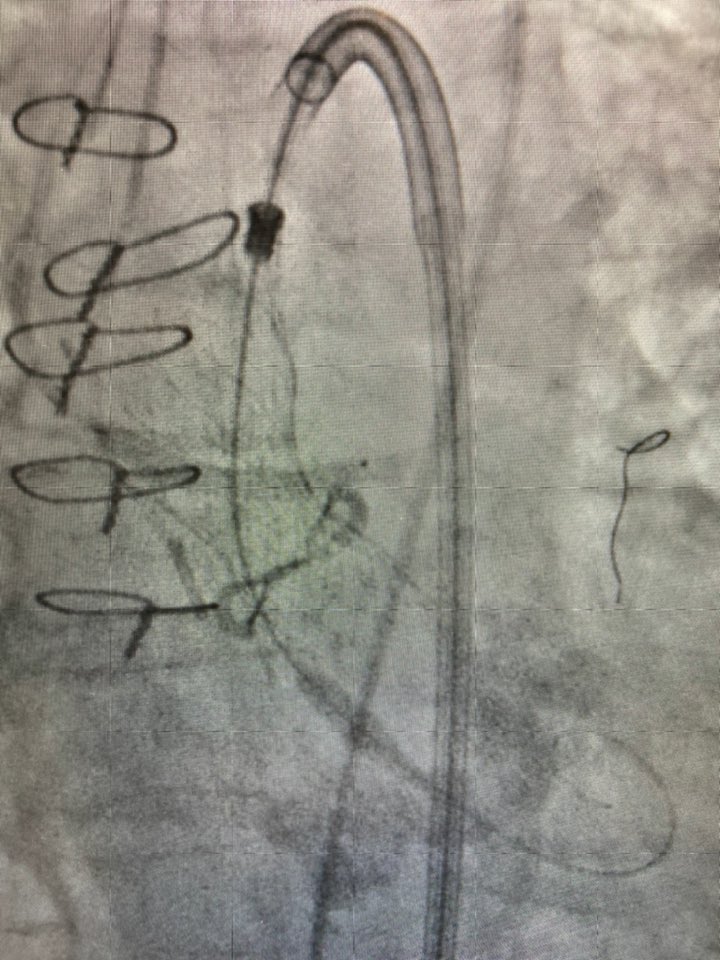

Glad for our first session of 3 Coronary Sinus Reducer cases with Pierre Barnay and Sébastien Armero at #HopitalEuropeen Marseille.

Thanks to @fra_giannini1 (our proctor) and @Neovasc team.